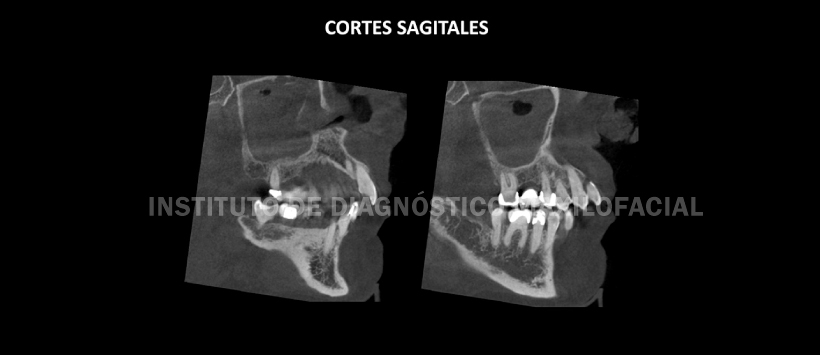

A la evaluación de la tomografía volumétrica en cortes axiales (Figura 2), coronales (Figura 3), sagitales (Figura 4) y transaxiales (Figura 5) se aprecia contenido isodenso en seno maxilar derecho con engrosamiento de las paredes óseas anterior, posterior y del piso sinusal; pérdida parcial de la pared medial, del cornete medio, inferior y del proceso uncinado; así mismo se aprecia compromiso del complejo osteo-meatal con obliteración del ostium e infundíbulo y contenido isodenso en fosa nasal derecho.